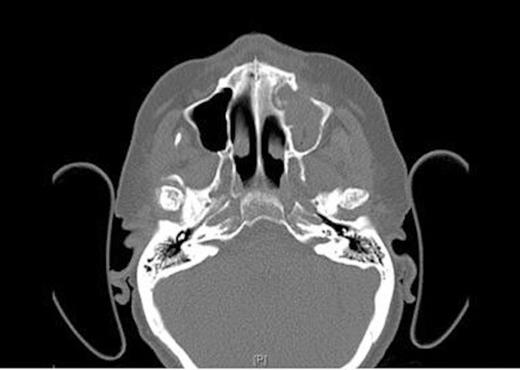

CT Scans (Fig. 1& 2) showed opacity and thickening of the left maxillary antrum with dehiscence of the medio-inferior and anterior walls of the sinus and a maxillo-oral fistula. There was destruction of bone in the floor of the left maxillary sinus consistent with an area of osteonecrosis secondary to bisphosphonate.

Axial CT Scan of the head showing osseo-sclerotic changes and defect in left maxillary sinus